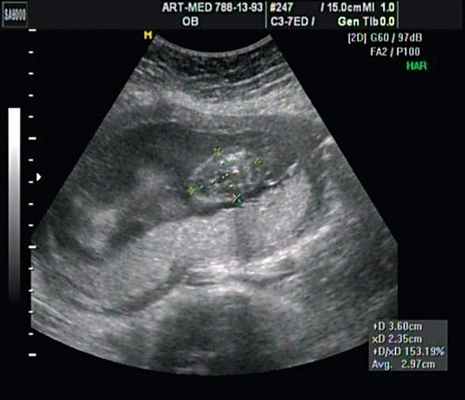

Данные КТ: к миелоцеле снизу и слева прилежит диспластичная дополнительная подвздошная кость, от которой отходят пучки мышечных волокон, идущие от ягодицы в дополнительную диспластичную нижнюю конечность, представленную аномально сформированными костно-хрящевыми структурами и пучками мышечных волокон. На расстоянии 19 мм от бифуркации аорты отходит подвздошная/бедренная артерия диаметром 1-1,5 мм, из которой дополнительная нижняя конечность получает кровоснабжение (рис. 3).

Учитывая типичную форму грыжевого выпячивания и отсутствие элементов нервной ткани, было высказано предположение о наличии у плода менингоцеле (рис. 16). Женщина приняла решение о прерывании беременности.

Рис. 16. Беременность 20 нед. Менингоцеле размером 37х21 мм.